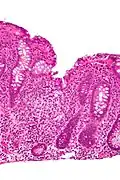

Micrograph showing cryptitis in a case of Crohn's disease. H&E stain.

In histology, cryptitis refers to inflammation of an intestinal crypt.

Cryptitis is a non-specific histopathologic finding that is seen in several conditions, e.g. inflammatory bowel disease,[1] diverticular disease,[2] radiation colitis,[3] infectious colitis.